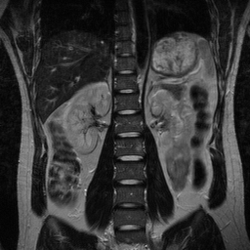

MixiMRI勉強会 脂肪抑制いろいろ 最近やっと勉強する気になったのですが、疑問が次から次へと出てきます。ここでは脂肪抑制についてお聞きしたいと思います。 脂肪抑制にもいろいろありますよね。 T2、PD、T1など。また、SE系、GRE系の違いもありま. ・骨盤部ではmriを,腹部ではctを第一選択にする. ・t1強調画像ではt1が長いほど磁化の回復が遅れるため信号が低く(黒く),t2強調画像ではt2 が長いほど磁化の減衰が遅れるため信号が高く(白く)描出される.t1とt2の組み合わせで組 t1強調画像はctの画像と似ており、脳の解剖学的な構造が見やすいという特徴があります。. 造影剤投与によりT1緩和時間が大きく短縮されますので基本的に脂肪抑制T1強調画像をベースに撮影が行われます。 ③実際の症例を提示します。 1) Stage I 腎細胞癌のdynamic MRI画像です。 左腎臓上極に1cm大の遷延性濃染する腫瘍を認めます。.

MRIは、磁気共鳴画像(Magnetic Resonance Imaging)の略称で、 強い磁石 と 電波 を使って体の断層像を撮る検査です。 MRIの原理は、まず強い磁気の中で、患者さんに外から電波を体に加えます。. ・骨盤部ではmriを,腹部ではctを第一選択にする. ・t1強調画像ではt1が長いほど磁化の回復が遅れるため信号が低く(黒く),t2強調画像ではt2 が長いほど磁化の減衰が遅れるため信号が高く(白く)描出される.t1とt2の組み合わせで組織 の成分が推定できる.. Mri造影剤は、mriにおける体内構造の可視性を向上するために使われる造影剤 。 コントラストの強調にはガドリニウムという化合物が最も一般的に使われる。 このmri造影剤は経口投与もしくは静脈投与(angio)により体組織内の核の緩和時間を短縮する。.

〈medix vol.50〉 41 1.はじめに mri検査において基本シーケンスはt2強調画像とt1強調 画像である。かかりつけ医の医療の場において、診断能向上の. 頭部MRI の基礎 -頭部MRI で撮られる各画像について- 友愛会南部病院 仁井田 明 要旨 現在、日常的に撮影されている頭部MRI(Magnetic resonance imaging :磁気 共鳴画像法)画像にはT1 強調像(T1WI)、T2 強調像(T2WI)、プロトン密度強 調像(PDWI)あるいはFLAIR(FLuid-Attenuated Inversion Recovery)像. 3T MRIの組織コントラスト能の特徴 T1強調画像 de Bazelaireらの研究 1) によると,腹部領域における3Tと1.5Tの緩和時間の違いは,肝臓,脾臓,膵臓では,3TでT1値が著明に延長するのに対し,筋肉では緩和時間に差がなく,結果的に,3Tでは肝臓,膵臓,筋肉でのT1値の差が少なくなる。.